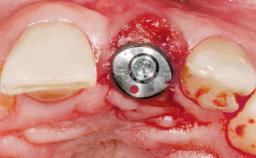

Immediate Flapless Placement of an Implant in a Maxillary Left Central Incisor Site

Placement Protocol Immediate implant placement

Tooth Site Maxillary incisor or canine

Socket Morphology Single-root socket

Socket Integrity Damage to one or more bone walls